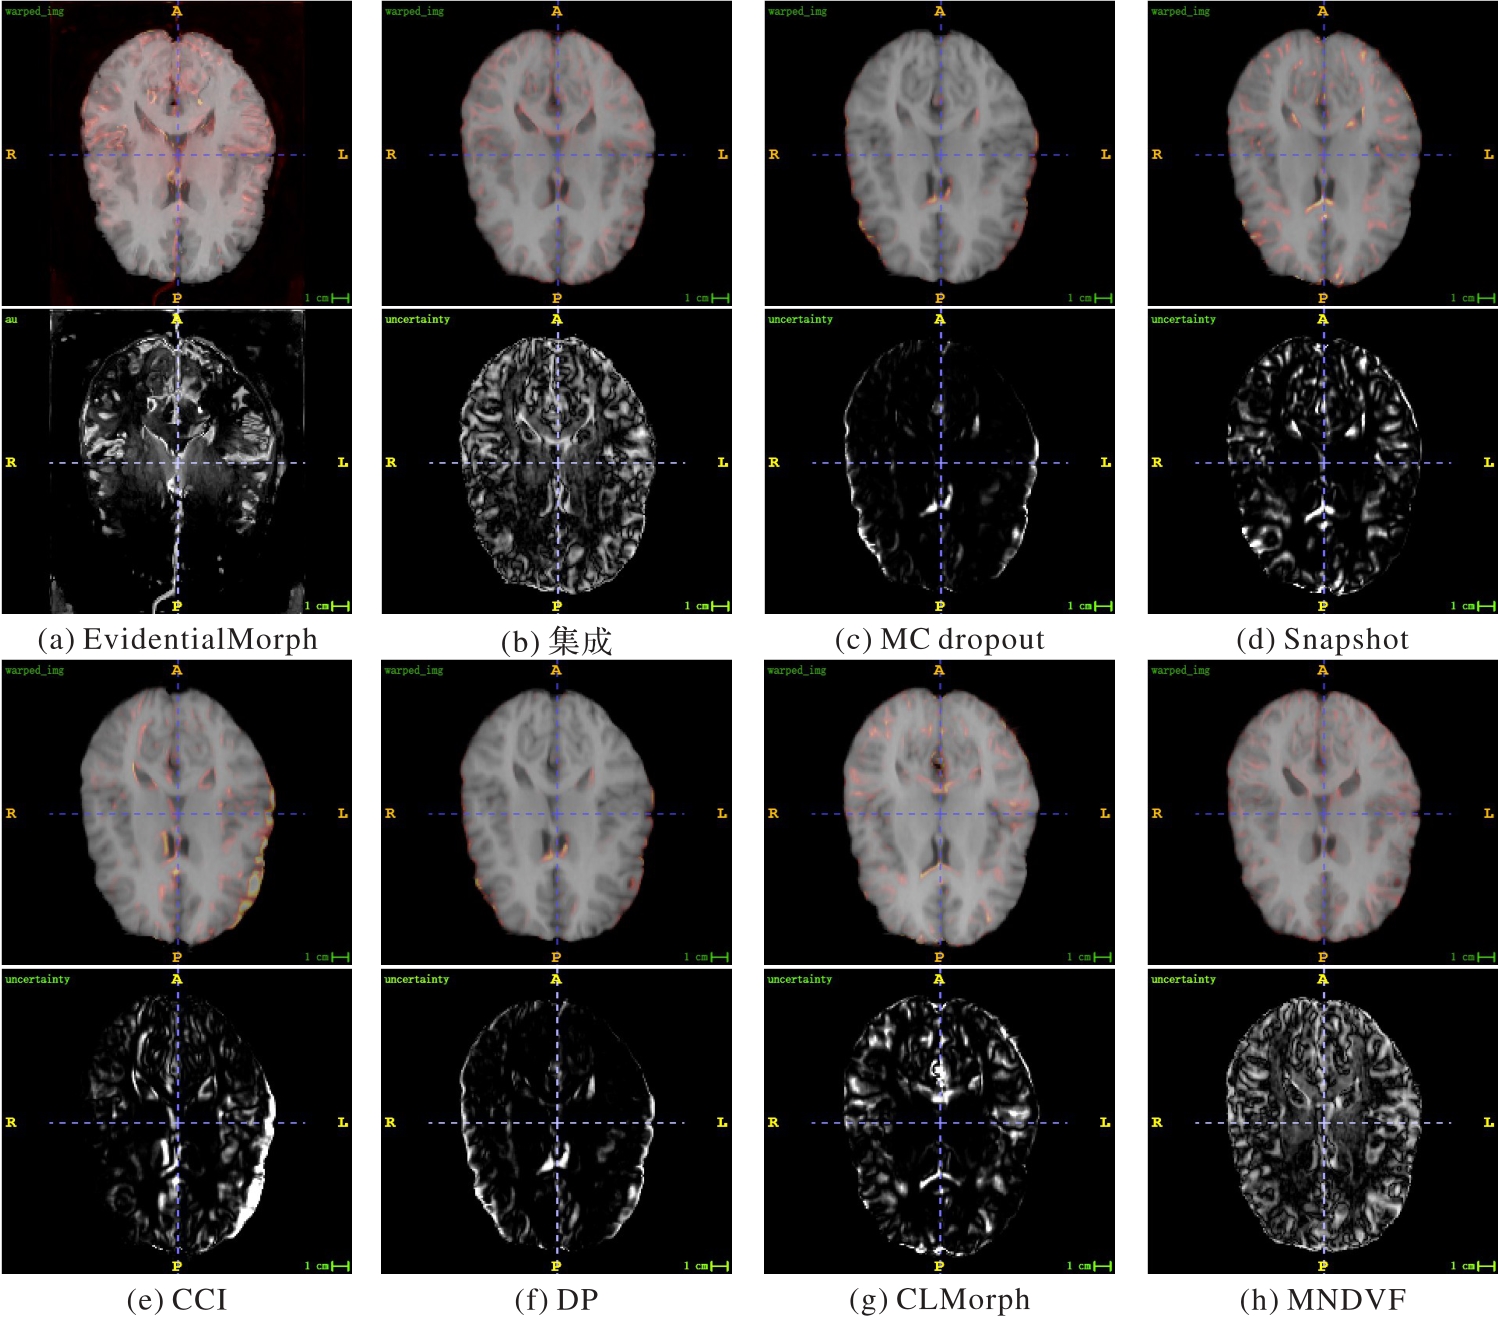

医学图像配准中的不确定性量化对医师在实际临床应用中评估风险至关重要。目前,基于深度无监督学习的医学图像配准模型虽然已经具备不错的效果,但仍缺乏在配准时估计外观不确定性的方法,这将影响配准的精度和可信度。此外,在实时性应用场景中,医学图像配准模型不但需要具备较高的配准精度,还需要快速进行推理。针对上述问题,提出一种基于证据深度学习(EDL)的不确定性感知无监督医学图像配准模型EvidentialMorph,将EDL应用于无监督医学图像配准。EDL是一种不确定性量化方法,无需额外的计算开销。首先,通过U-net架构的配准主干网络模块学习得到形变向量场(DVF);其次,通过一种改进的空间变换器网络(STN)模块——证据STN模块学习配准图像的正态逆伽马(NIG)分布,从而直接计算出配准图像及其外观不确定性。在海马体、LPBA40和IBSR18核磁共振成像(MRI)数据集上的实验结果表明,与CLMorph模型相比,在配准精度上,EvidentialMorph的Dice相似性系数(DSC)最高提升了3.31%,归一化交叉相关(NCC)系数最高提升了2.75%;在推理时耗上,EvidentialMorph减少了85 ms。以上结果验证了EvidentialMorph能够快速得到有效的不确定性量化结果,并提升配准精度,为实时医学图像配准场景提供了不确定性量化的可能,可以改善配准效果。